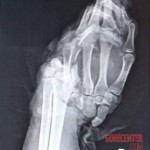

Woman crushed her entire hand in the accident. The plastic surgeons did an excellent job to fix her hand. While the hand will never be aesthetically pleasing again, the functionality will largely remain. The photos show the entire healing process.

Date: 06/06/2024 Views: 7479 Comments: 3 Votes: 6

Category: Accidents, Mutilation